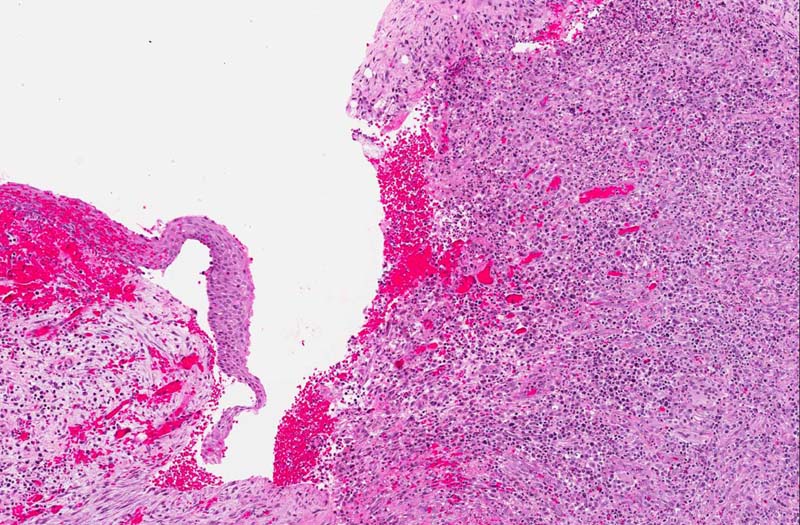

Hematoxylin & eosin

Area 1: Note that there the covering squamous epithelium is thin and free of dysplastic changes. The basal layer is composed of columnar cells with hyperchromatic nuclei, columnar shape, vague palisading arrangement (arrow). A small amount of fibrinous exudate (f) is present in between the squamous epithelium and the underlying stroma. This is not part of the classic features of this type of cyst but rather a result of the inflammation.

• The specimen is composed of stroma composed of fibroconnective tissue lined by a thin squamous epithelium about 5-8 cells thick (area 1). There are some chronic inflammatory cell infiltration in the stroma. Note that parakeratosis (nuclei in surface keratin) is present.

• The basal layer of epithelial cells is composed of hyperchromatic cuboidal to columnar-appearing cells with a tendency for nuclear palisading (area 1 and 2).

• In some are of the specimen, there is chronic ulcer and inflammatory changes and not covered by epithelium. This finding reflects the inflammatory nature of the patient's clinical condition. Although this type of cysts typically have mild to moderate inflammation in the cyst wall, ulcer associated with intense inflammation is not a classic features and the inflammation here is most likely resulted from infection.